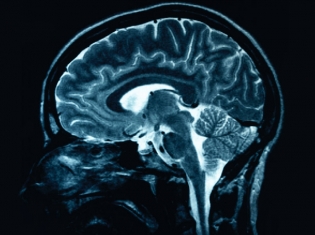

(RxWiki News) Patients who receive brain stents after a stroke have a much higher chance of suffering another stroke or dying. Receiving aggressive medical therapy was found to be more than twice as effective.

However, 14.7 percent of patients in the angioplasty and stenting group experienced a stroke or died during trial enrollment in comparison to 5.8 percent in the group that received only aggressive monitoring. Over the course of the trial between November 2008 and April 2011, 33 patients had a second stroke or died within 30 days of joining the study versus 13 patients in the group that received only therapy.

A follow up period of less than a year showed that 21 percent of patients who received the Gateway-Wingspan stent, the only one approved for high risk stroke patients, had a stroke or died. About 12 percent from the medical group had another stroke or died.